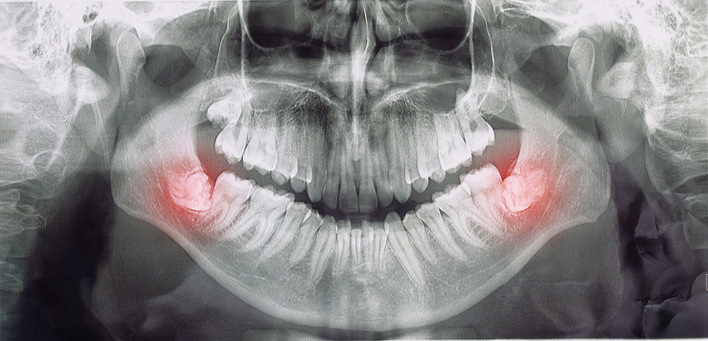

DVT nicht als Standard vor Entfernung retinierter Weisheitszähne zu fordern

Aus forensischer Sicht kann eine DVT-Aufnahme vor der Entfernung retinierter und verlagerter Weisheitszähne nicht als Standard gefordert werden, erklärte Stefan Haßfeld, Geschäftsführer und ärztlicher Direktor der Klinik für Mund-, Kiefer- und Gesichtschirurgie am Klinikum Dortmund, auf dem 17. MKG-Update-Seminar am 30. und 31. Januar 2026 in Wiesbaden.